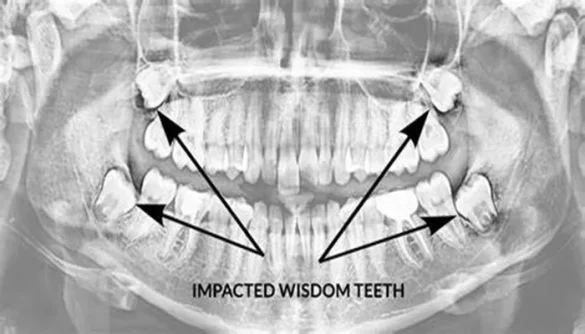

For many people, wisdom teeth can become impacted, meaning they don’t have enough space to emerge properly. When this happens, the teeth may cause a variety of issues, which is why dental professionals often recommend their removal. In this article, we will explore the reasons why impacted wisdom teeth need to be removed and the potential consequences of leaving them untreated.

Impacted wisdom teeth are those that have not fully erupted through the gums or have become misaligned. This can occur for a number of reasons, including insufficient space in the mouth, abnormal tooth growth, or a lack of gum tissue for the tooth to break through. Impacted wisdom teeth may be partially erupted, meaning they are visible but not fully out, or fully impacted, where the tooth is trapped under the gum or bone.

X-ray findings: Dentists may use X-rays to assess the position of the wisdom teeth and determine if they are causing or will cause problems in the future.